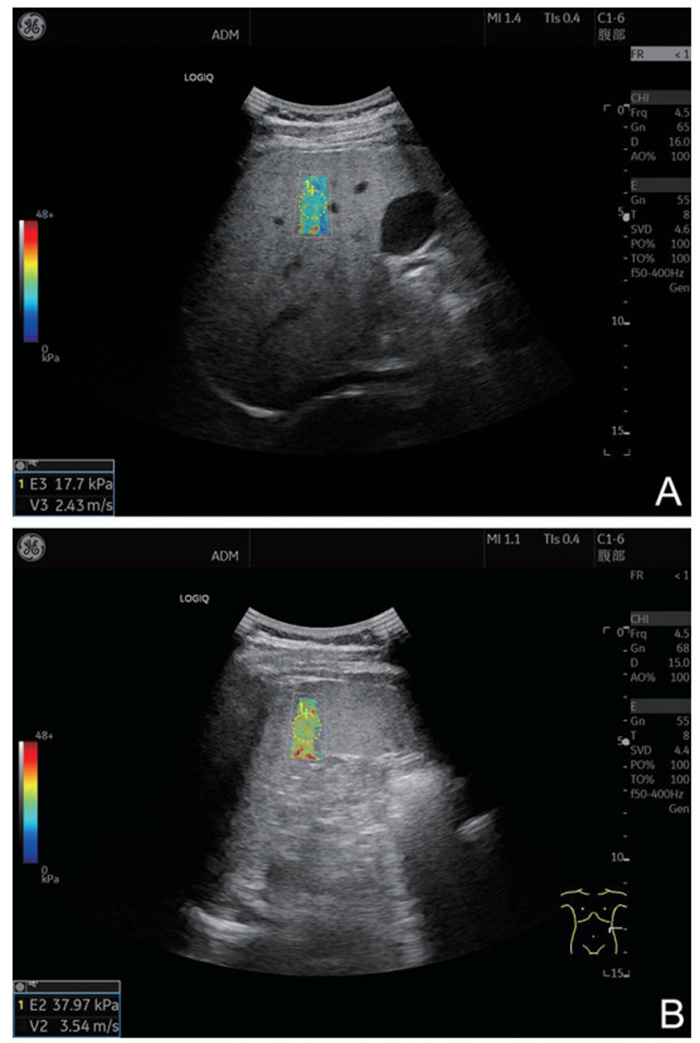

Construction of risk model of esophageal and gastric varices rebleeding in cirrhosis based on 2D-SWE

GUO Li, LOU Junge, YAN Yuanyuan

2025, 23(12): 2042-2045. doi: 10.16766/j.cnki.issn.1674-4152.004287

83 4

Abstract:

Objective  The pathophysiological mechanism of esophageal and gastric varices (EGV) rebleeding in liver cirrhosis is complex, and the mortality rate is high. Identifying the literature factors of EGV rebleeding is important to reduce the mortality rate. Two-dimensional shear wave elastography (2D-SWE) can evaluate the degree of liver hardness and pathological changes in a non-invasive and quantitative manner. This study discusses the construction of the EGV rebleeding risk model based on 2D-SWE to provide a reference for clinical prevention and treatment.  Methods  A total of 162 patients with EGV with cirrhosis admitted to Zhengzhou Central Hospital Affiliated to Zhengzhou University from January 2020 to December 2022 were selected. According to whether rebleeding occurred, the patients were divided into the no rebleeding group (127 cases) and the rebleeding group (35 cases). The risk factors of EGV rebleeding in patients with cirrhosis were analyzed by Logistic regression. To construct a nomogram prediction model for the EGV rebleeding in cirrhotic patients, and evaluate the prediction efficiency of the nomogram model.  Results  The proportion of Child-pugh grade A liver function, the proportion of mild esophageal and gastric varices and the level of ALB in the group without rebleeding were higher than those in the group with rebleeding (P < 0.05), and the proportion of first ligation, liver hardness and spleen hardness in the group with no rebleeding were lower than those in the group with rebleeding (P < 0.05). Logistic multivariate results showed that Child-Pugh grade of liver function, liver hardness, spleen hardness, and ALB were independent influencing factors for EGV rebleeding in cirrhosis (P < 0.05). A nomogram model for predicting EGV rebleeding in cirrhosis was established according to the logistic multi-factor results, and the model was verified. ROC curve analysis results showed that the C-index of the nomogram model was 0.903 (95% CI: 0.846-0.975), and the measured value of the nomogram model was basically consistent with the predicted value, with high predictive value and good clinical effectiveness.  Conclusion  2D-SWE detection of liver and spleen hardness is a risk factor for EGV rebleeding, and the prediction model based on this nomogram has a good predictive effect on EGV rebleeding.